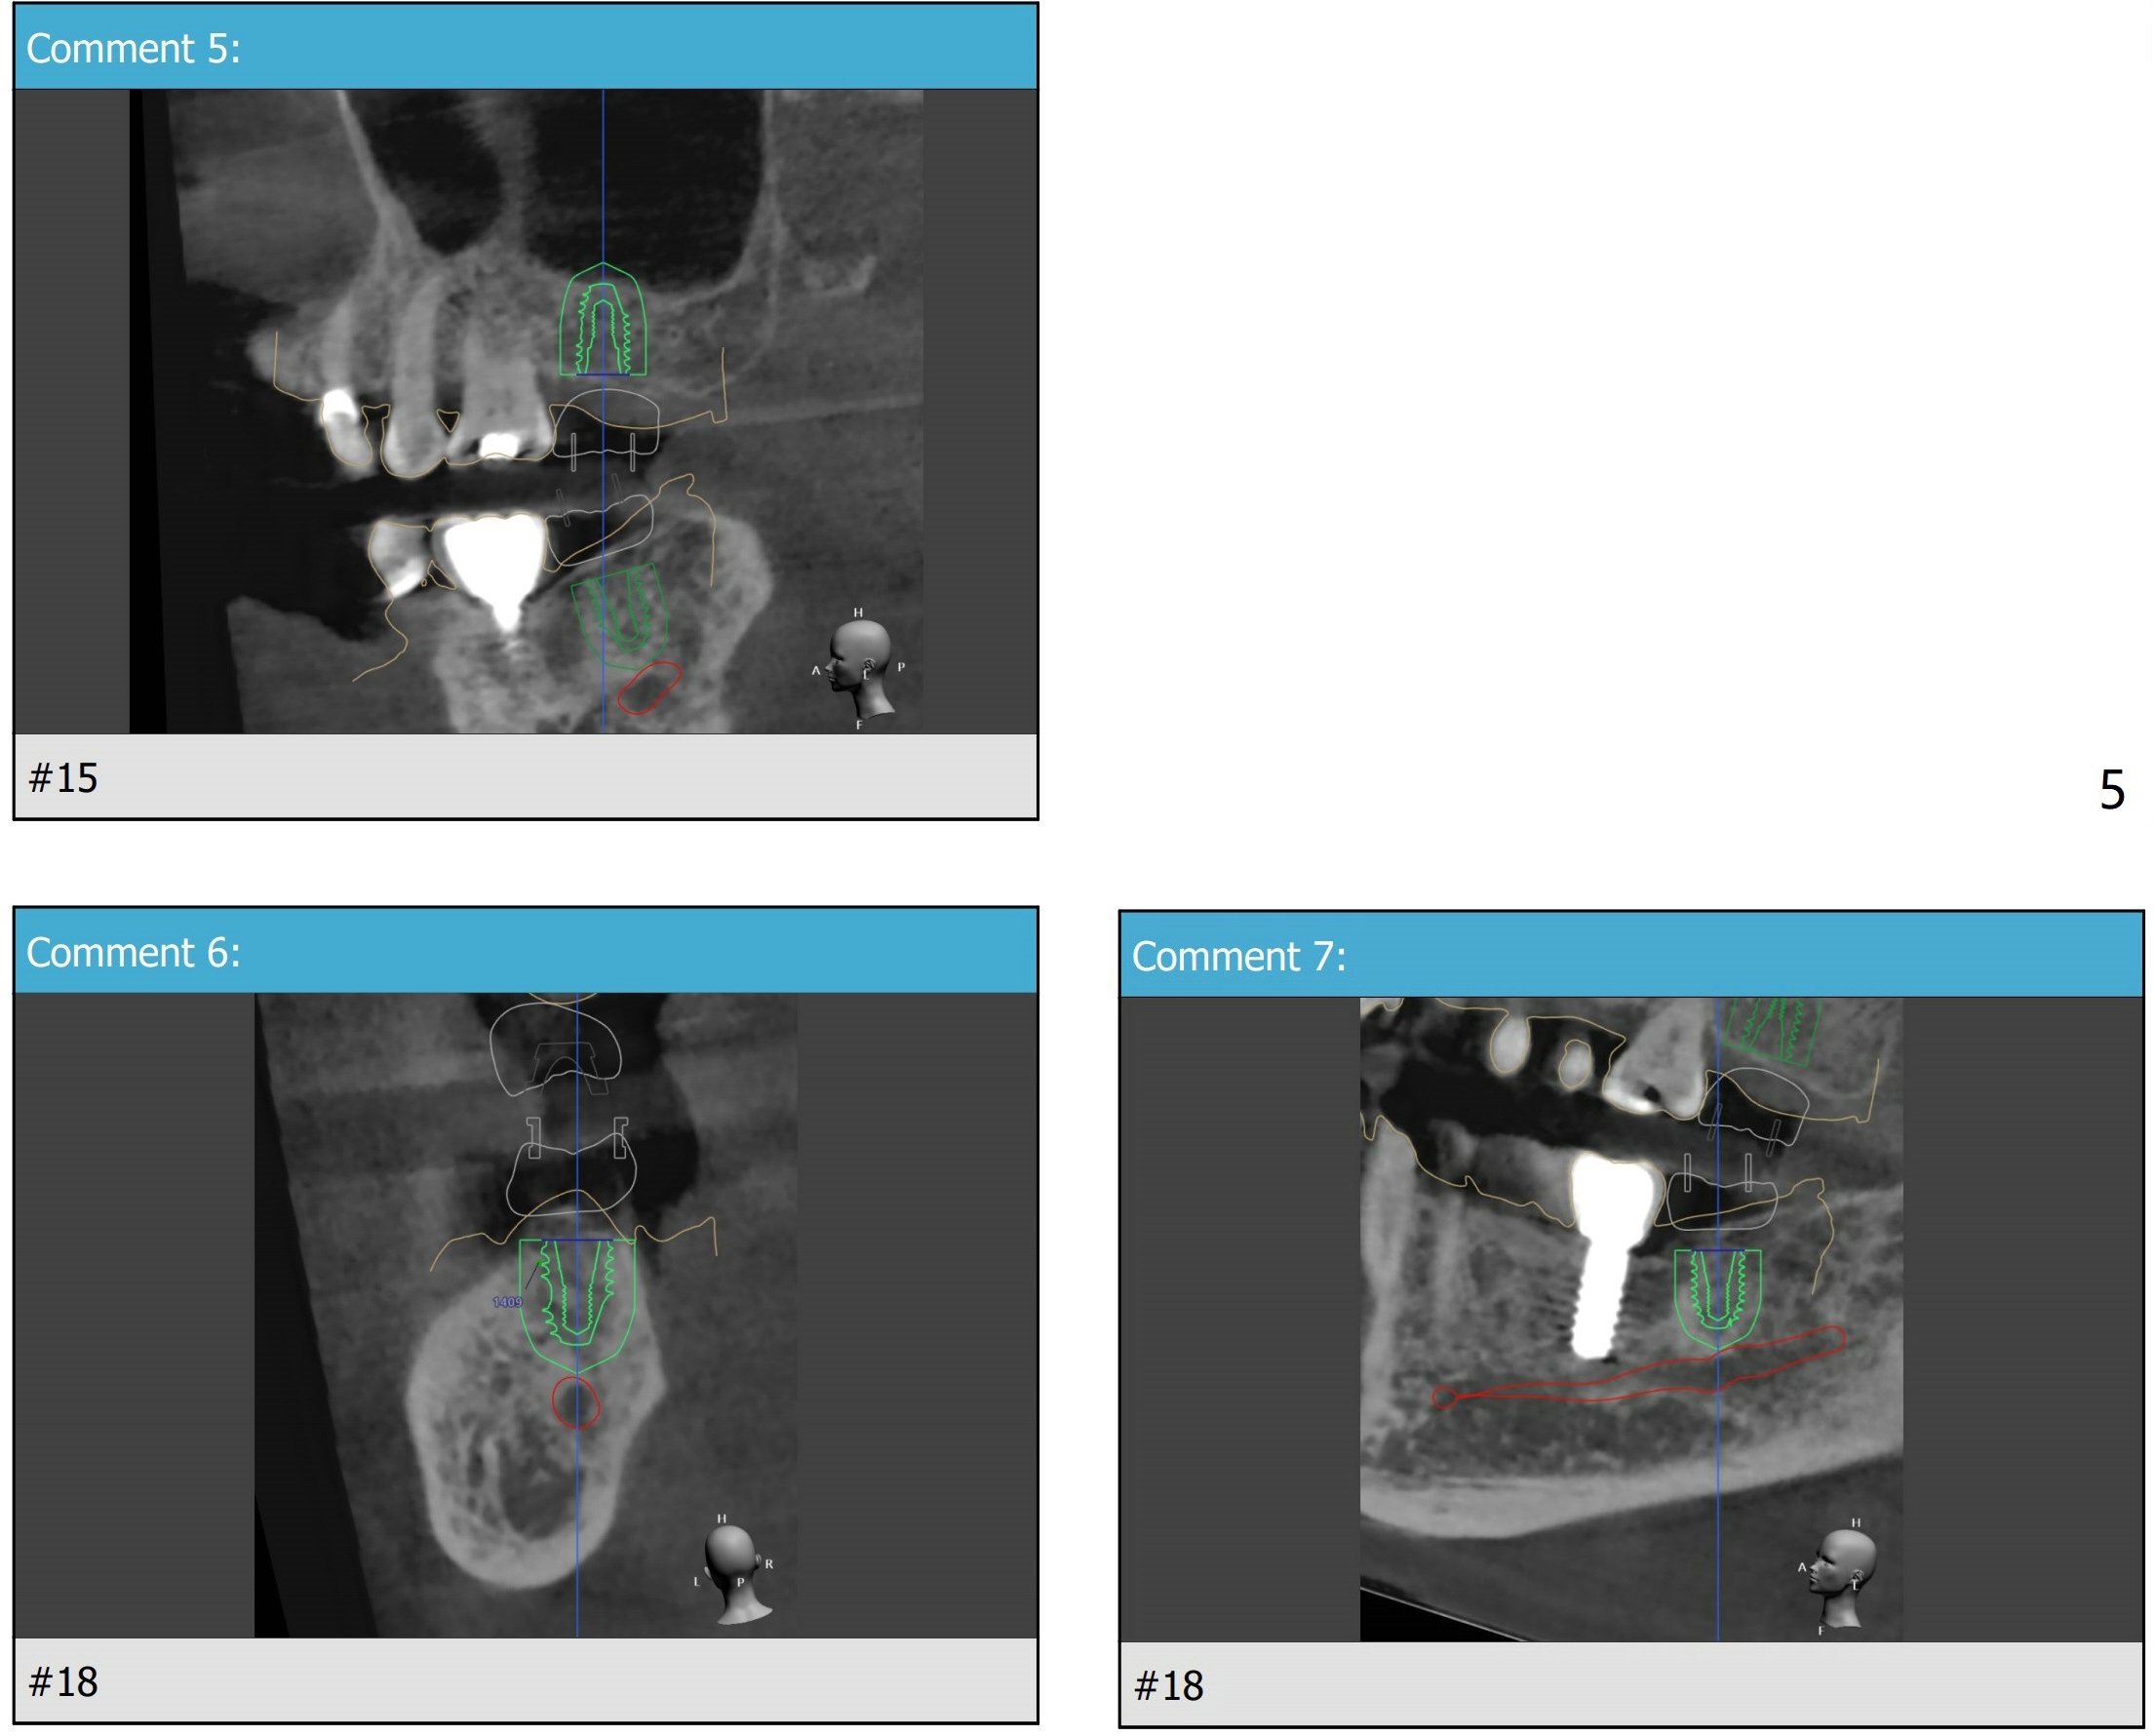

Short Implants

A 73-year-old woman